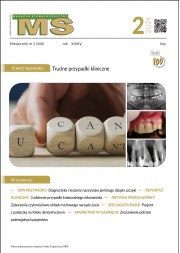

Na kontrolnym zdjęciu rentgenowskiemu wykonanym po wypełnieniu kanału nie rozpoznał perforacji, choć należy przyznać, iż było to dość trudne. Wynikało z faktu, iż operator wypreparował sztuczny kanał w osi właściwego kanału korzeniowego i w związku z tym po jego wypełnieniu obraz materiału umieszczony w kanale perforacyjnym nałożył się na obraz kanału naturalnego (ryc. 1A). Oczywiście doświadczony diagnosta prawdopodobnie zauważyłby niewielkie ilości uszczelniacza poza zarysem kanału i w celu pogłębienia diagnostyki wykonałby zdjęcie rentgenowskie w projekcji skośnej (ryc. 1B), która uwidoczniłaby perforację, lub zdecydowałby się na wykonanie badania CBCT, które wnosi zdecydowanie więcej informacji niż zdjęcie zębowe (ryc. 2A, B). Taką decyzję podjął zresztą endodonta, który wykonał CBCT. Badanie wykazało wypełniony materiałem sztuczny kanał perforacyjny położny dowargowo od nietkniętego kanału naturalnego. Ponieważ wynik badania wrażliwości miazgi prądem faradycznym nie różnił się od zębów sąsiednich, endodonta poinformował pacjenta, że ponowne leczenie może ograniczyć się wyłącznie do usunięcia gutaperki i zamknięcia perforacji. Ostatecznie jednak nie udało się uniknąć leczenia endodontycznego, a ze względu na trudności usunięcia gutaperki od strony jamy zęba wykonano zabieg chirurgiczny i usunięto ją od zewnątrz.

Ryc. 1. Możliwości diagnostyczne wewnątrzustnego zdjęcia zębowego. A. Zdjęcie wykonane w projekcji ortoradialnej. Obraz radiologiczny ćwieka gutaperkowego nakłada się na obraz światła kanału korzeniowego, co może sugerować prawidłowo wykonane leczenie endodontyczne. Wątpliwości budzą niewielkie ilości uszczelniacza poza zarysem wypełnienia. B. Zdjęcie wykonane w projekcji skośnej, które uwidacznia kanał perforacyjny wypełniony materiałem oraz nietknięty kanał właściwy.